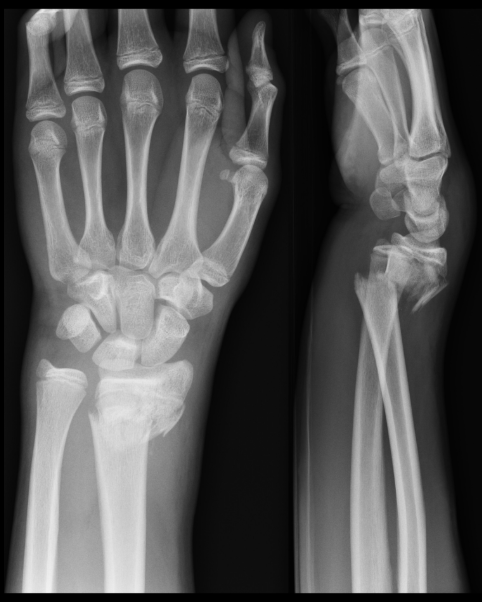

A Colles’ fracture is one of the most common types of wrist fractures, especially among older adults. It typically occurs when a person falls on an outstretched hand, causing the distal radius (the larger forearm bone) to break near the wrist joint.

It involves a fracture of the distal radius with the broken fragment angling upward (dorsally).

Often described as a “dinner fork” deformity due to the shape the wrist takes after the injury.

X-ray is the gold standard to confirm the fracture and evaluate displacement.

In complex cases, a CT scan may be recommended.